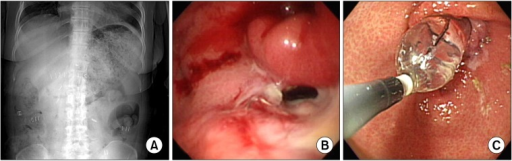

GastroparesisXray.jpg

X-ray showing a large amount of food in the stomach due to severe gastroparesis[1]